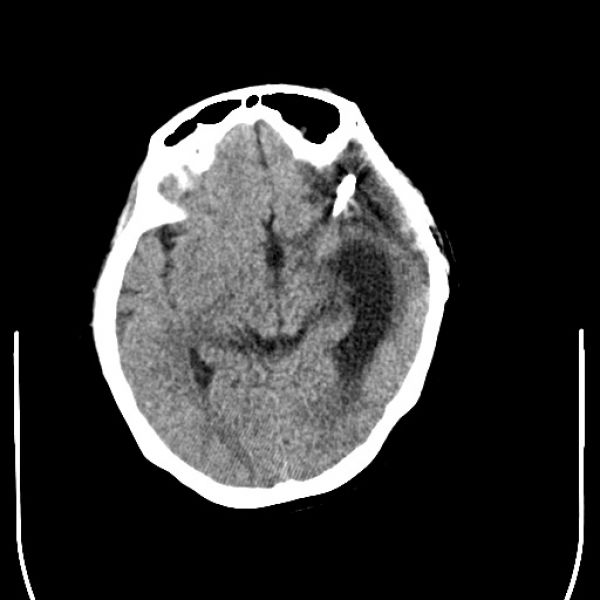

病区主任朱英杰高度重视,认为患者此次主要以头痛不适住院,结合既往病史,考虑头痛与颅内动脉瘤仍有一定的关系,与家属仔细商议病情后,建议复查全脑血管造影。由田志副主任完成了选择性全脑血管造影术,术中发现左侧大脑中动脉M1段分叉部可见一动脉瘤夹影,M1段分叉部可见一囊状动脉瘤,右侧颈内动脉眼动脉段可见一小动脉瘤。患者颅内多发动脉瘤!且是短时间内的复发,若动脉瘤一旦“爆炸”,病情会急剧恶化,患者愈后则极差。

经过与患者家属的详细沟通和精心准备后,由朱英杰病区主任主刀、田志副主任医师一助,有条不紊的在显微镜下分离血管,小心保护神经组织,最终历时4小时,完成左侧大脑中动脉M1段分叉部动夹闭+包裹术,术后在神经外科二病区及ICU医师的共同精心治疗下,患者逐步恢复好转,得益于良好的神经显微技术,患者未出现新发的神经功能缺失,3周后步行出院。